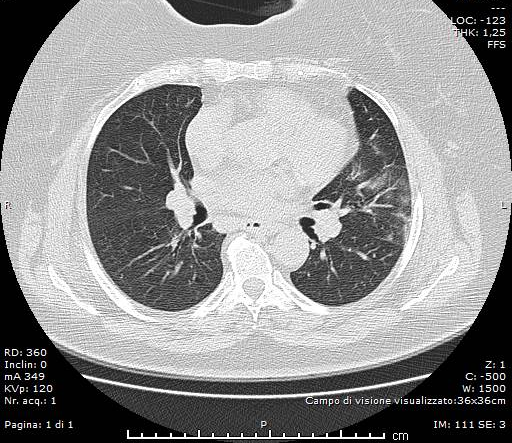

Si esegue d’urgenza, a completamento diagnostico, indagine TC del Torace in condizioni basali ed algoritmo ad alta risoluzione (HRCT), con scanner a 64 strati, le cui immagini ottenute sono state analizzate con slice-thickness di 1,2 mm e successive ricostruzioni MPR (assiali, sagittali e coronali).

HRCT ha documentato, in entrambi i parenchimi polmonari, la presenza di plurimi addensamenti con aspetto “a vetro smerigliato” ed alcune aree con pattern “crazy-paving”, per la coesistenza di aree “ground-glass”, di consolidamento ed ispessimento interstiziali. Trachea e bronchi pervi. Qualche piccolo linfonodo, reattivo, in sede ilo-mediastinica. Immagine cardiaca nei limiti. Non evidenza di versamento pericardico. Minimo versamento pleurico basale bilaterale.

La TC ha messo bene in evidenza, inoltre, il “segno ragnatela” (“spider web sign”), rappresentato da un’area di opacità ground-glass, ad aspetto grossolanamente triangolare ed angolare, in sede basale sub-pleurica a destra, con all’interno setti interlobulari ispessiti come una rete; la pleura adiacente era stirata ed ispessita, denotando una forma simile a quella di una ragnatela nell’angolo.